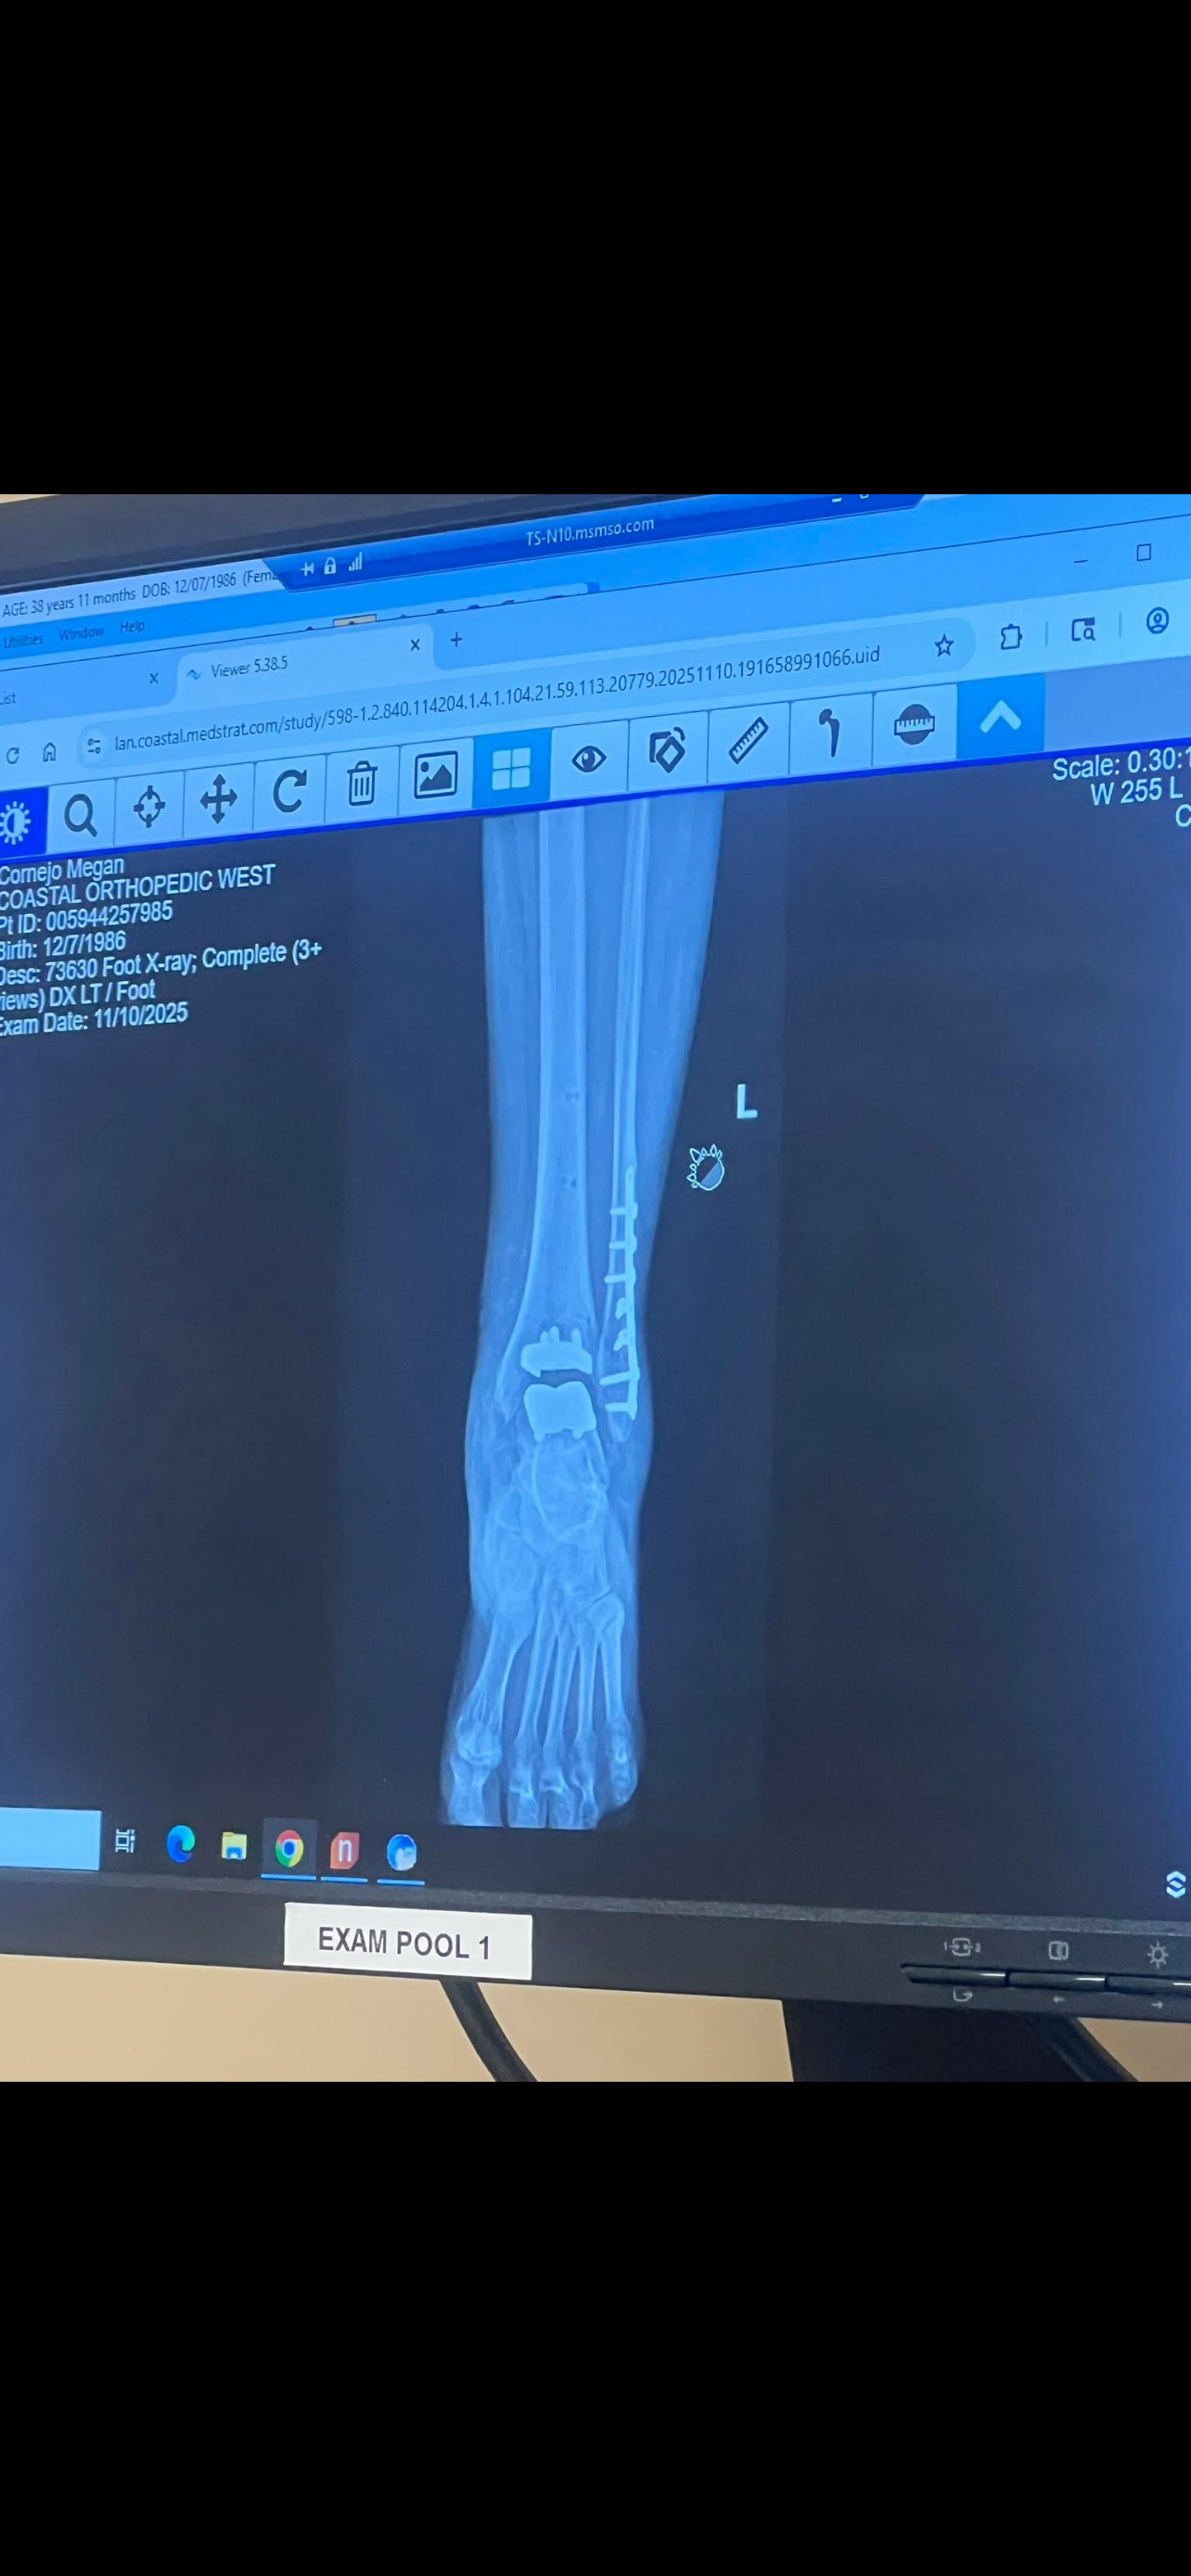

Back in October, I had an ankle replacement that was supposed to be a straightforward recovery. Instead, a blister developed that never healed, and everything quickly spiraled from there. Since then, I’ve had three additional surgeries, with a possible fifth still ahead. Doctors have had to remove dead tissue and perform multiple skin grafts, including an Integra graft and another graft just four weeks ago. Despite everything, the wound still isn’t fully healed, and I remain completely non-weight-bearing.

During this process, I was also diagnosed with a vascular artery condition that affects circulation, which may be part of why my wound has struggled to heal.